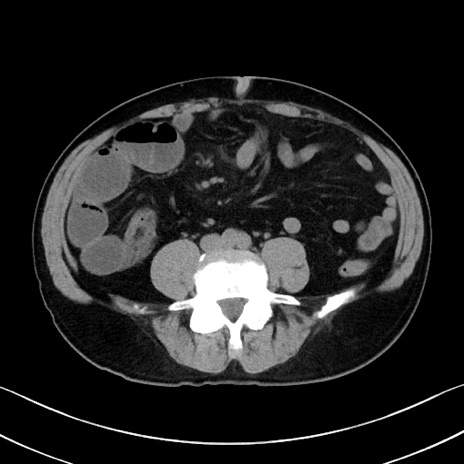

症例35(横断像)

【症例】70歳代 男性

【主訴】腹部膨満、嘔吐

【現病歴】昨日より腹部膨満感出現。本日増悪し、仙痛出現。嘔吐あり、受診。

【既往歴】糖尿病、胆摘後

【身体所見】BP 149/80mmHg、HR 74/min、BT 35.9℃、腹部:膨満、軟、圧痛なし。腸雑音減弱あり。上腹部正中切開瘢痕あり。

【データ】WBC 13500、CRP 1.72

冠状断像